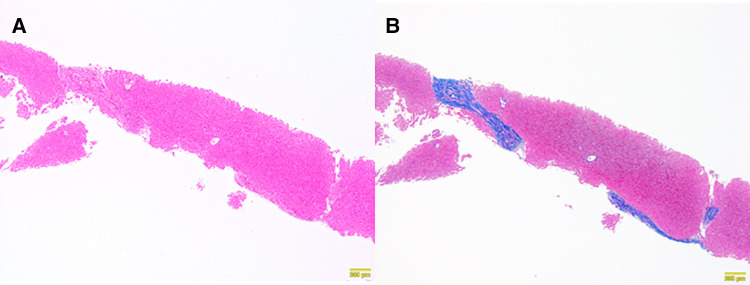

Clinical course after discharge

At 6 months after laparoscopic extrahepatic bile duct resection and hepaticojejunostomy, she was readmitted and underwent needle liver biopsy to confirm the morphological improvement after surgery. After discharge from the hospital, her hepatic function normalized, and her cholinesterase level, which was low before surgery, showed a tendency toward improvement; however, her NH3 level remained above the normal range (Table 1). A histopathological examination showed mild improvement of chronic hepatitis and fibrosis (F2-3A1) (Figures 3A,B). The patient was regularly followed at the outpatient clinic.